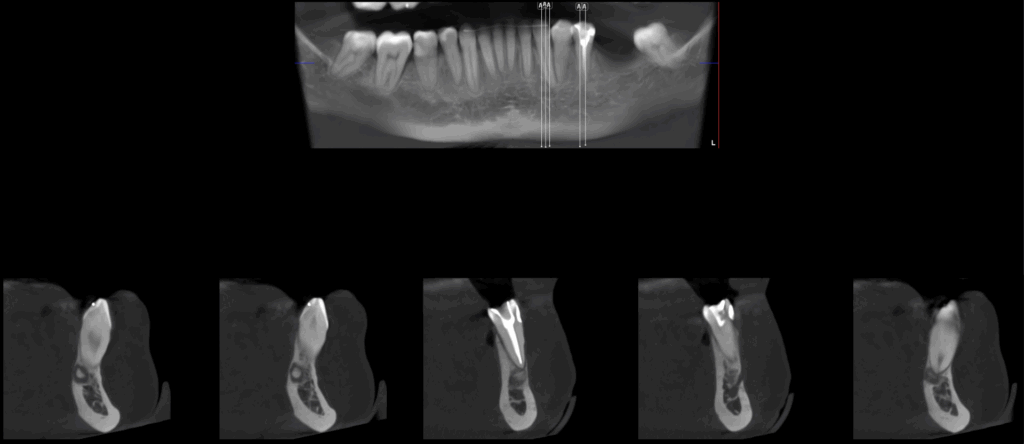

A la evaluación de la tomografía volumétrica (CBCT) en los cortes axiales (Figura 2) y transaxiales (Figura 3), se aprecia imagen mixta localiza a nivel apical de pieza 33 de limites definidos, que ocasiona adelgazamiento de tabla ósea lingual, así mismo se observa imagen mixta a nivel apical de pieza 35 y próximo a conducto dentario inferior, de limites definidos, que ocasiona adelgazamiento de tabla ósea vestibular

CORTES TRANSAXIALES